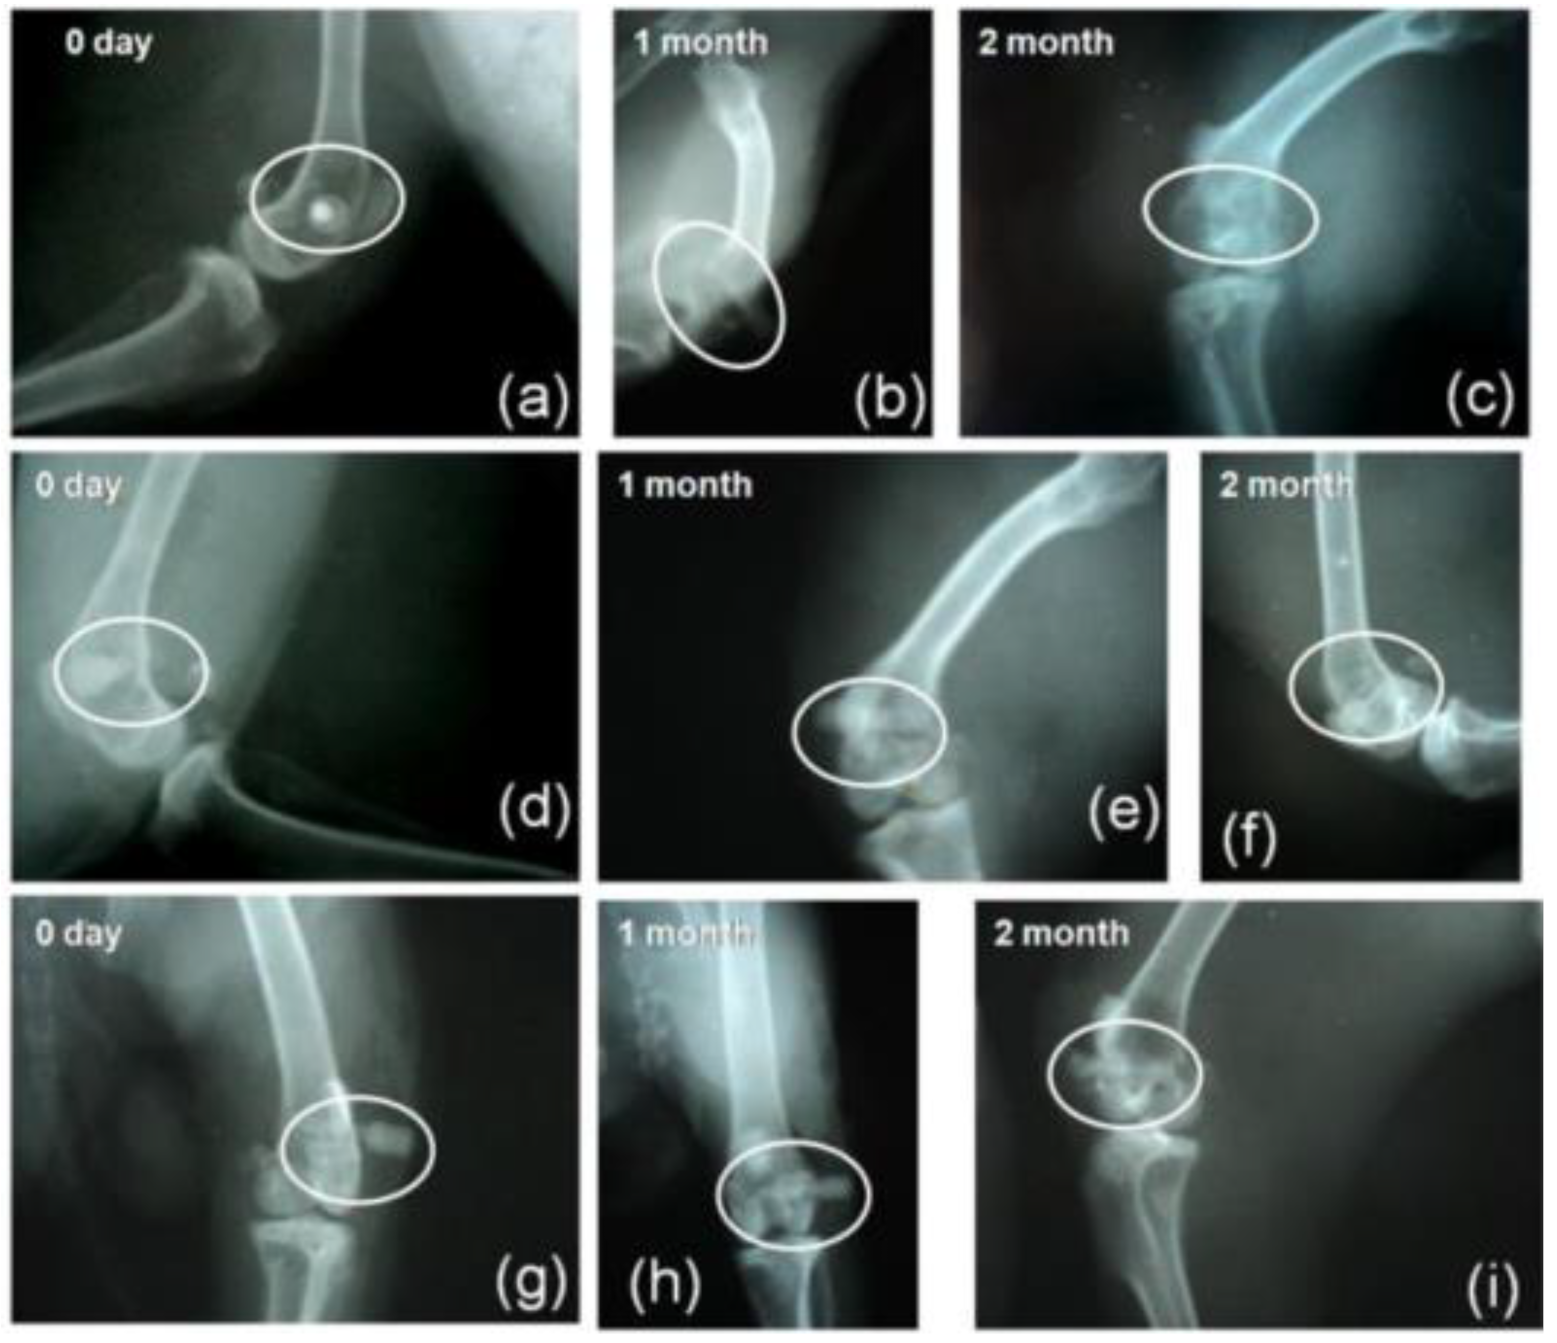

Mahato et al. [156] compared a magnesium-based metallic implant (Mg-Zn-Ca) (BM) with and without HAp (BMH) and bioactive glass S53P4 (BMG) coatings. Figure 10 shows the radiograph of the samples in a femoral bone defect in mice. It is possible to observe that the BM degrades after 2 months of surgery but appears as a radiodense material on the day of implantation (day 0). The BM implant was radiopaque over the 2 months of implantation despite a distinct radiolucent gap between the bone and the implant (Figure 10). It is noticeable that the BMG-coated implant presented the highest radiopaque density among the other implants (Figure 10). In addition to improved radiopacity, the authors reported a superior corrosion resistance in vitro, evaluated by the lowest Icorr (68 µA) and Ecorr (−296 mV) values compared to BMH samples (Icorr = 297 µA; Ecorr = −1420 mV). In addition, the enhancement of the apatite precipitation capacity on the Mg alloy samples was observed, corroborating the bone formation verified by the biological tests.

5.6. Zinc (Zn)